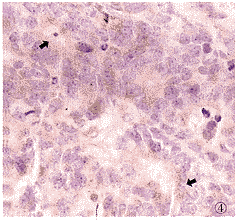

原發性皮膚免疫細胞瘤組織病理:真皮和皮下組織內瘤細胞浸潤,在原發性皮膚免疫細胞瘤中大多呈片狀或團塊狀;在繼發性皮膚免疫細胞瘤中常呈瀰漫性,除見少數組織細胞和嗜酸粒細胞以及很多肥大細胞外,表現為在以小淋巴細胞的背景中出現:

1.較多漿細胞樣淋巴細胞,核內或胞漿內有對MGP和PAS呈陽性反應的物質(免疫球蛋白)。

2.較多甚至很多散在的漿細胞。漿細胞樣淋巴細胞和(或)漿細胞的百分比在原發性皮膚免疫細胞瘤中占20%,多位於浸潤灶周圍,在繼發性皮膚免疫細胞瘤中占40%

3.尚見一些向漿細胞分化的不同階段的細胞(具有不規則形胞核的中心細胞中心母細胞免疫母細胞特殊漿細胞和漿母細胞)的混合形浸潤。多形性較明顯,核分裂象亦較多見免疫標記示漿細胞樣淋巴細胞和漿細胞合成單克隆C3受體和IgG(少數病例中IgA或IgM)瘤組織內免疫球蛋白(大多為IgMK型)增加。

4.免疫組化:特點為腫瘤細胞表達單型胞漿免疫球蛋白重和輕鏈分子。免疫細胞瘤,瘤細胞表達CD70但缺乏CD50浸潤內漿細胞CD20-。大多數病例可查到免疫球蛋白基因重排。